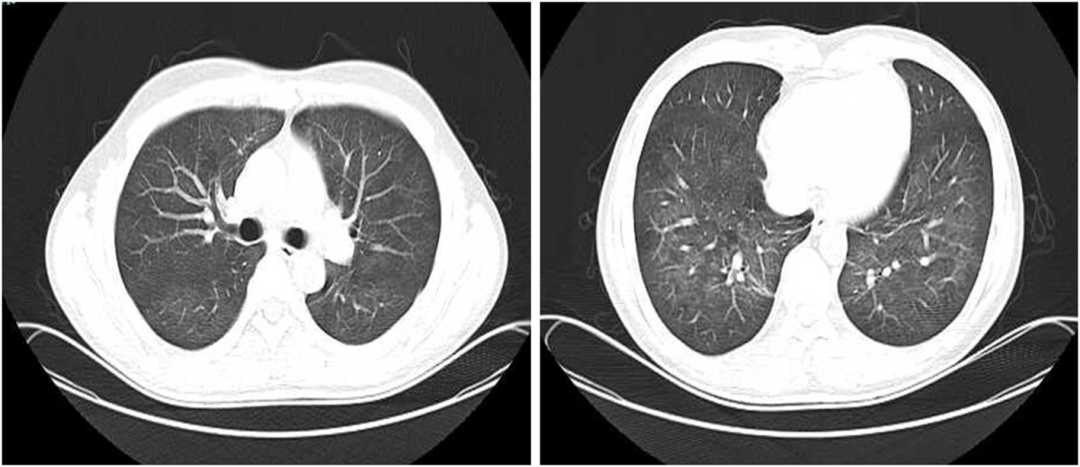

• 胸部CT显示左上肺有一个厚壁空洞,可见血管集束征和局部胸膜增厚(如图1所示)

图1:治疗前胸部CT显示左上肺厚壁空洞,内缘光滑,外缘不规则,邻近胸膜和左下胸膜增厚

接受静脉注射头孢曲松(2g,每日一次)治疗2周,口服磺胺甲恶唑-甲氧苄啶(0.96g,每日两次)。治疗一周后胸痛缓解。治疗6周后,胸部CT扫描显示肺空洞消失,只留下少量斑片状浸润。胸膜增厚情况有所改善(图2)。

图2:治疗6周后胸部CT显示空洞消失,仅留下少量斑片状浸润,胸膜增厚改善